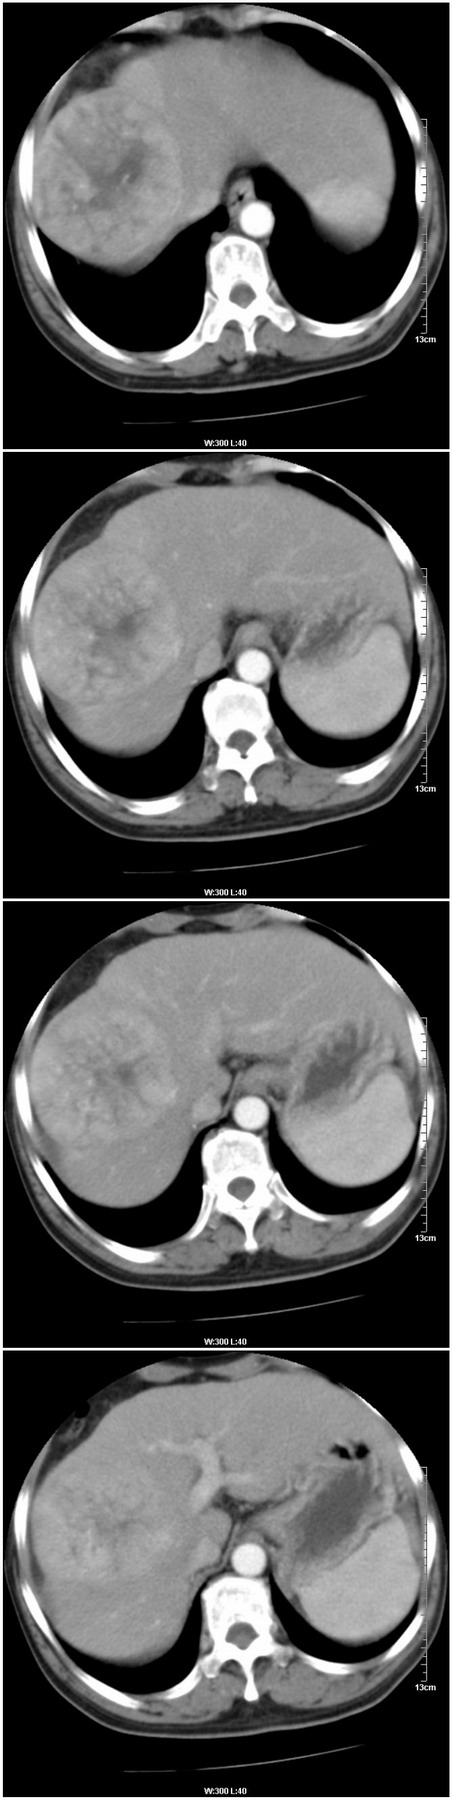

标题: [肝脏占位]CT13576:男性,57岁。胸腹痛伴消瘦半年余。 [打印本页]

标题: [肝脏占位]CT13576:男性,57岁。胸腹痛伴消瘦半年余。

肝右叶巨块型肝癌

巨块型肝癌

增强情况:

病灶密度变化 正常肝组织密度变化

平扫病灶平均ct值:51.3hu 56hu

动脉期: 74.2hu 69hu

门脉期: 85.9hu 102 hu

4分钟后: 71.8hu 76hu

9分钟后: 71.9hu 72.9hu

这是又一例门脉期强化比动脉期强化明显的病例。往常我们所见到的都是由于肝癌是动脉供血,所以病变常在动脉期明显强化,而在门脉期就会下降。但是这一例和过去做过的一个病例都是在门脉期更明显强化,请战友们分析这种变化的实质。有人提出这是正常肝组织逐渐向肝癌转化的一个过程,也有人说这是另一种肝癌的类型,就是相对于一动脉供血为主的肝癌来说,这是一种以门脉供血为主的一种肝癌类型。战友们说说看,你认为怎样解释这种情况更合适呢?

病变周围可见环状强化,先考虑:肝癌。

鉴别:肝腺瘤、局灶性结节增生。

1.肝右叶巨块性病变,周围有假包膜,内部密度不均,有坏死,增强后以门脉期强化明显,反应以门脉供血的特征,为不典型肝癌(梁索性)。

1.肝右叶巨块性病变,周围有假包膜,内部密度不均,有坏死,增强后以门脉期强化明显,反应以门脉供血为主的特征,为不典型肝癌(梁索性)。

考虑板层型肝癌可能性,建议穿刺活检.因为可见假包膜及病灶内可见纤维组织,强化类型符合肝癌形式